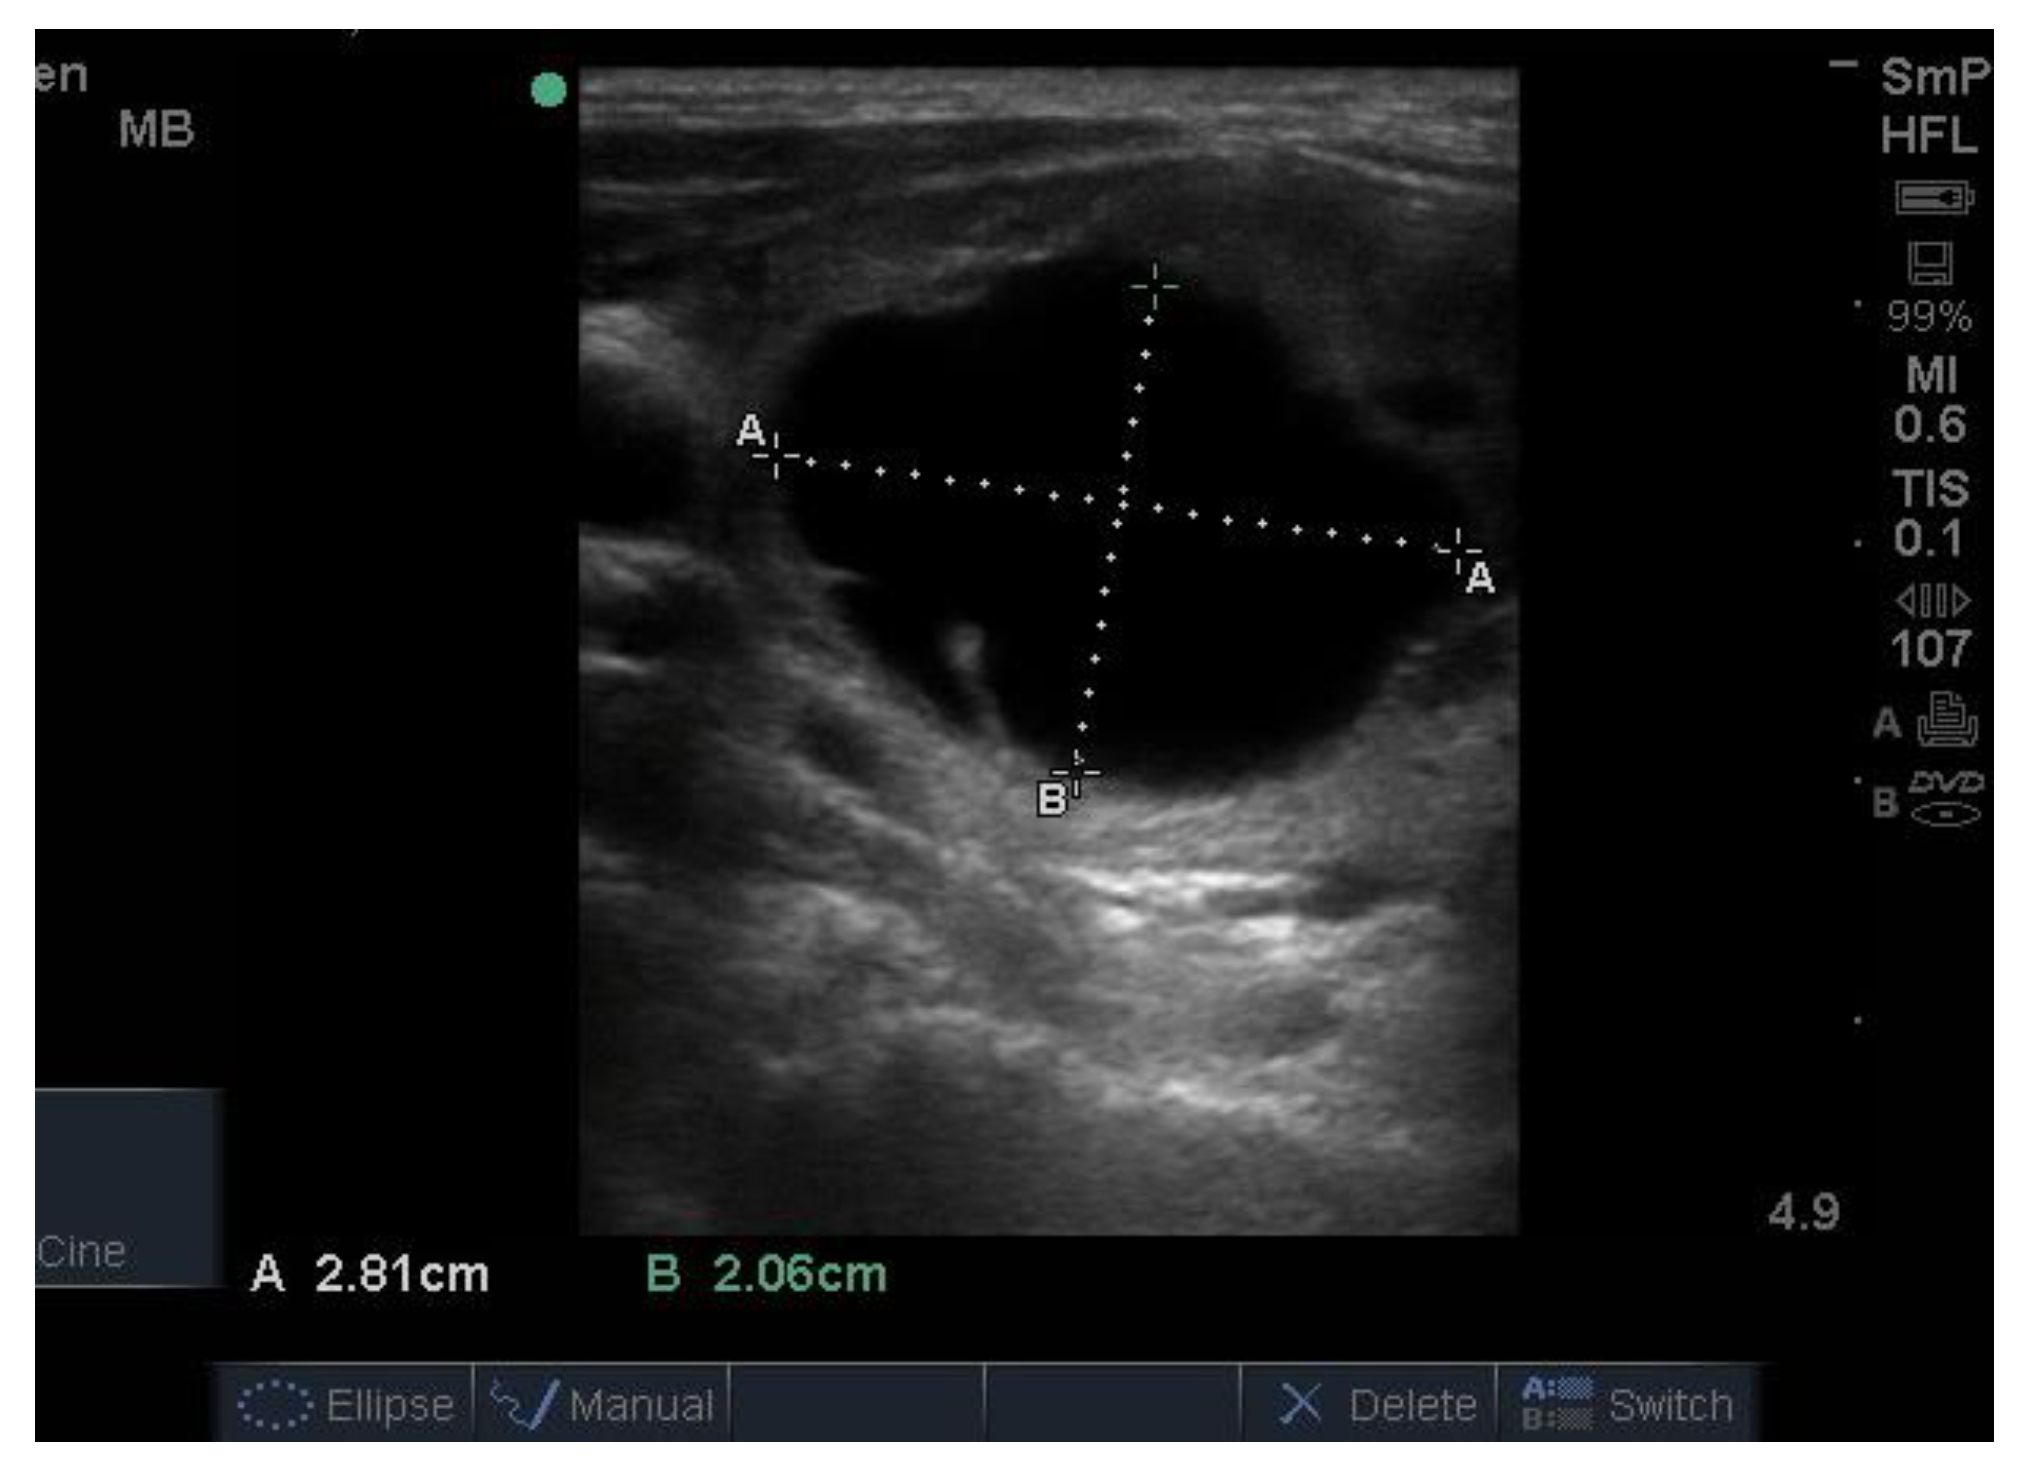

6. Thyroid Cysts

Thyroid cysts are important because it may be possible to relieve the patient’s neck symptoms by removing the fluid. However, a cyst tends to refill, which can be a sign that it has a solid component which, in about 10% of cases, is cancerous [6]. Sometimes it is difficult to differentiate a cyst from a hyperechoic colloid or “toxic” nodule, even after biopsy, since fluid may be drawn off from both lesions. Both may look hypoechoic (black) but a cyst is usually larger and more round, somewhat blacker and has a thin, sharp edge, as shown in Figure 6. The cyst has a specific feel on palpation (whereas a colloid nodule, where palpable, feels firm, even hard) and, if tested for, is translucent. Cysts may have a solid component whose echogenicity may be hypo or hyper echoic, sometimes only seen after removal of the fluid.

Figure 6.

Large thyroid nodule of mixed appearance, i.e., comprising both solid (lower half) and cystic (upper half) components. FNAB of the solid component showed that the lesion was benign, whereas biopsy of the upper region obtained a large amount of chocolate coloured fluid.